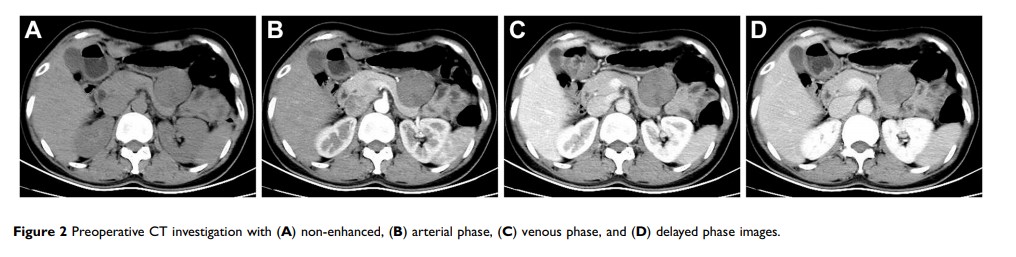

十二指肠胃肠道间质瘤的最优化的腹腔镜处理和肿瘤学结局:胰十二指肠切除术或保留胰的十二指肠切除术?